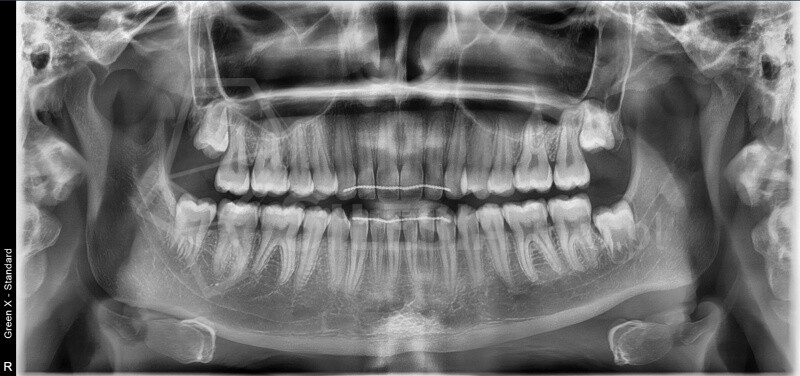

Zdjęcie panoramiczne (pantomogram) obejmuje całe uzębienie i szczęki, pokazując zmiany, których nie widać na zdjęciach punktowych RTG – takie jak torbiele, guzy, stany zapalne czy zwyrodnienia stawów.

To podstawowe badanie profilaktyczne, które warto wykonywać regularnie – przynajmniej raz na dwa lata.